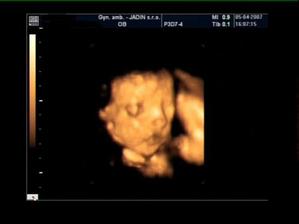

Náš malý Samko